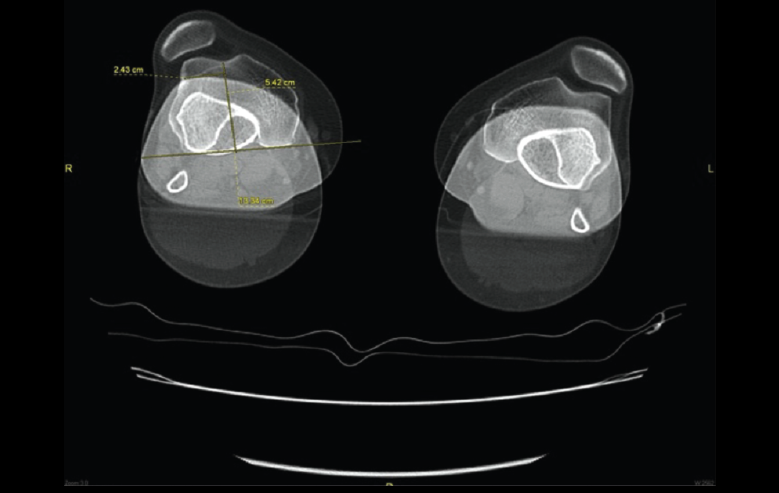

5.1. TA-GT (tuberosidad tibial anterior-garganta de la tróclea)

En pacientes sintomáticos con inestabilidad rotuliana, la TAC es útil para medir la TA-GT(10). La distancia TA-TG es una medida radiológica propuesta por Goutallier y Bernageau que sirve para cuantificar el ángulo Q. Consiste en medir la distancia en milímetros de la tuberosidad tibial anterior a la garganta de la tróclea proyectadas sobre una línea que pasa por los bordes posteriores de ambos cóndilos femorales, superponiendo 2 cortes axiales de TAC. Es una medida fiable y reproducible pero poco precisa, con un margen de error de más de 4 mm. La distancia TA-GT es mayor de 20 mm en el 56% de las inestabilidades rotulianas y tan solo en el 3% de la población sana(11)(Figura 28).

Figura 28. Corte axial de tomografía axial computarizada con superposición de imágenes con rótula y parte posterior de cóndilos y tuberosidad tibial anterior, que nos permite medir la distancia TA-GT, en condiciones normales hasta 2 cm.

5.2. Balance rotuliano

Mide la inclinación de la rótula en relación con el borde posterior de los cóndilos femorales (Figura 29).

Figura 29. Corte axial de tomografía axial computarizada con superposición de imágenes con rótula y parte posterior de cóndilos y tuberosidad tibial anterior, que nos permite medir el tilt o balance rotuliano, en condiciones normales hasta 20°.